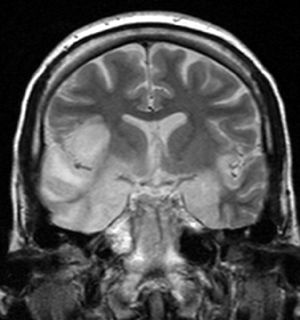

| coronal T2-weighted MR image shows high signal in the temporal lobes including hippocampal formations and parahippogampal gyrae, insulae, and right inferior frontal gyrus. A brain biopsy was performed and the histology was consistent with encephalitis. PCR was repeated on the biopsy specimen and was positive for HSV | |